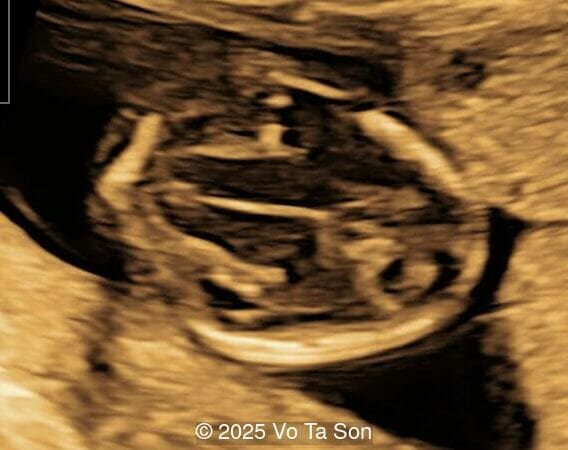

- Open spina bifida in the sacral region with dry brain and crash sign, BS/BSOB >1, direct lesion at sacral coccygeal spine